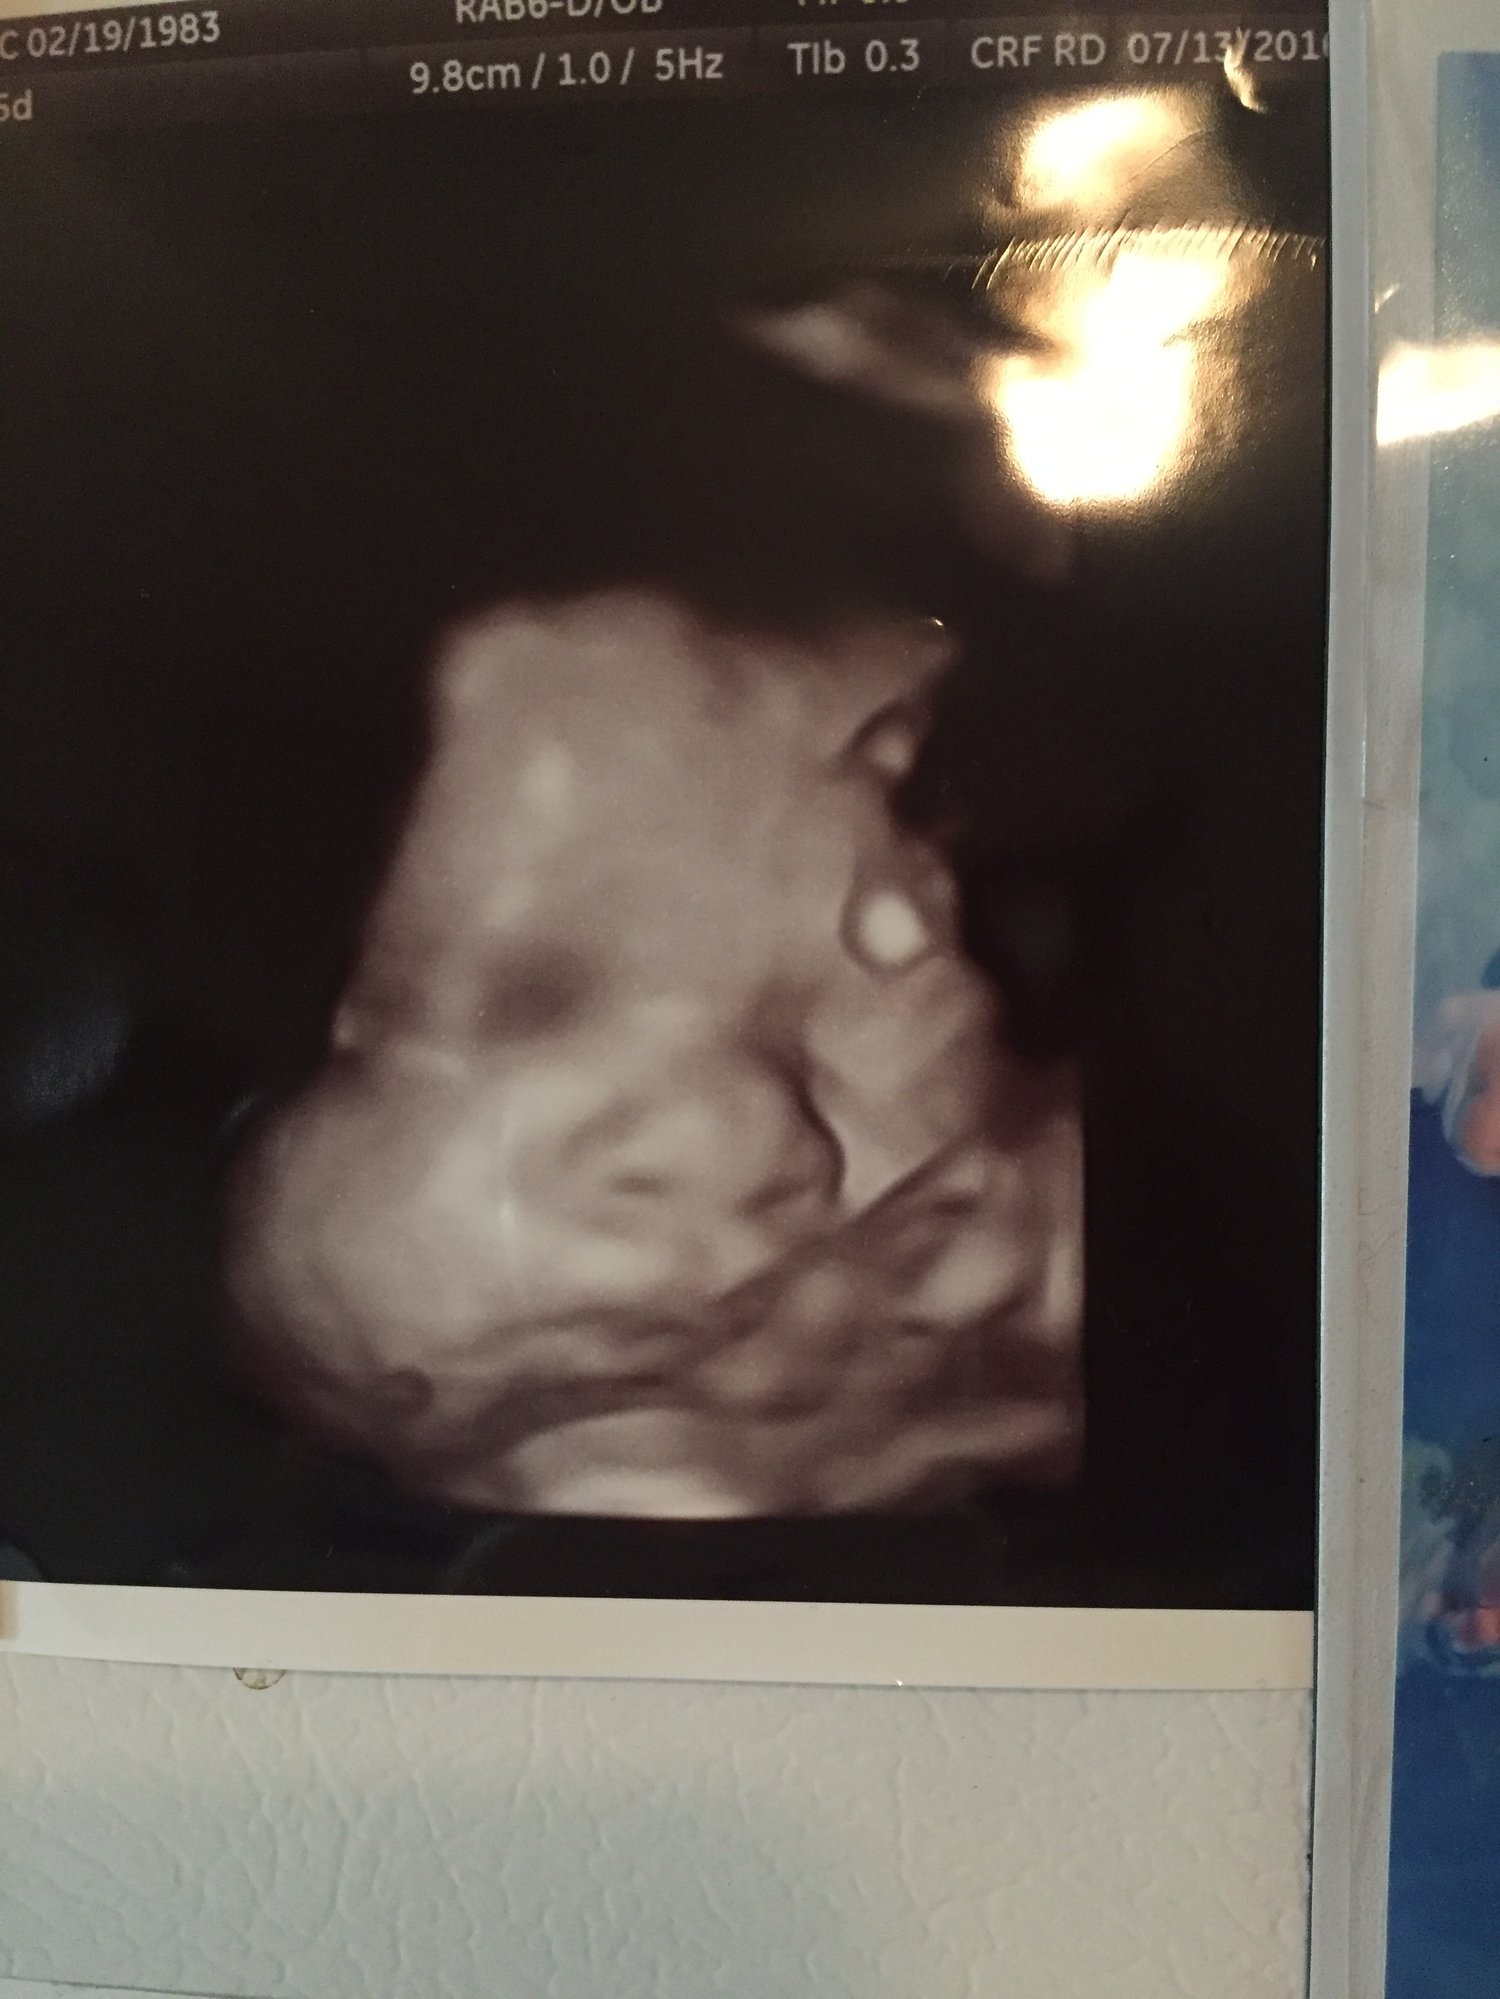

Sorry if giant. 3D ultrasounds are a bit weird but it was so cool to see his face. He has my lips for sure and his daddy's nose. Taken at 25w3d